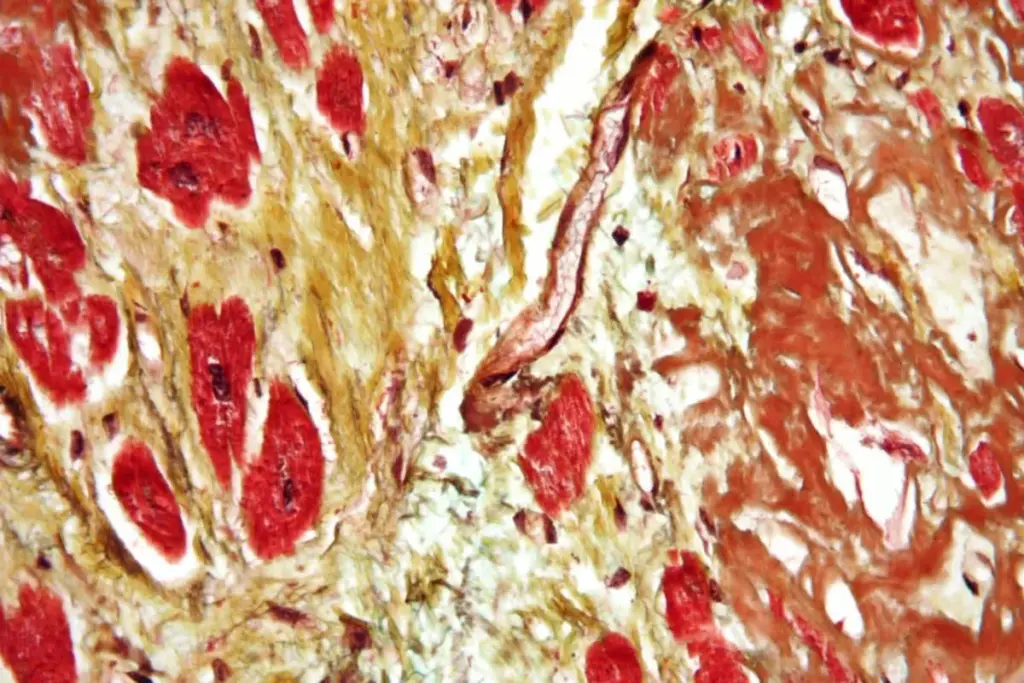

PAD is caused by the narrowing or blockage of arteries due to plaque buildup. This reduces blood flow to the limbs, causing symptoms and serious problems if not treated.

The disease involves the vascular endothelium, inflammation, and lipid metabolism. Atherosclerosis, the main cause, is linked to smoking, diabetes, high blood pressure, and high cholesterol.